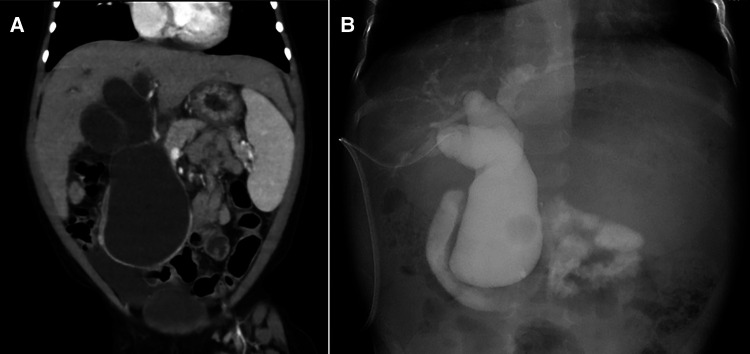

Contrast-enhanced computed tomography showed dilation of the common bile duct (maximum diameter: 5 cm) (Figure 1A), suggesting CBD. However, her laboratory data on admission showed severe liver disfunction (AST, 79 IU/L; ALT, 43 IU/L; γ-GTP, 491 mg/dl; D-bil, 0.3 mg/dl; Alb 2.5 mg/dl; CHE, 90 IU/L; NH3, 123 μg/dl) (Table 1). The Child-Pugh classification was equivalent to Grade A–B when combined with the fact that she had consciousness disturbance, a history of vitamin K treatment, and her laboratory findings at the time of admission. We initially performed laparoscopic exploration and bile drainage via the gallbladder, noting severe hepatic fibrosis resembling end-stage liver cirrhosis (Supplementary File S1). A 5-mm 30° laparoscope was inserted through an umbilical incision along with a 5 mm trocar with a multichannel port device (E.Z Access/LAP-PROTECTOR minimini; Hakko Co., Ltd., Tokyo, Japan). Since the view of the lower liver space could not be obtained, a 3-mm port was additionally inserted through the EZ Access to secure the view. The liver had many hoop-like notches on both lobes, which is a finding of liver sclerosis. A 3-mm port was additionally inserted into the right upper abdomen and the gallbladder was pulled out from the port wound. A double purse suture was applied with 4–0 PDS outside the body and an incision was made, and then an 8-Fr balloon catheter was inserted, and the tip was placed in the common bile duct. After placing a drainage tube in the gallbladder, cholangiography was performed. We confirmed continuity between dilation of the intrahepatic bile ducts and the common bile duct, and it consistent with findings of biliary dilatation. There was no gallbladder atrophy, which is seen in I cyst-type biliary atresia (Figure 1B). Cholangiography revealed Todani type IVa CBD with pancreaticobiliary maljunction. Then, the patient received liver-supporting therapy and nutritional support for 7 weeks before definitive surgery.